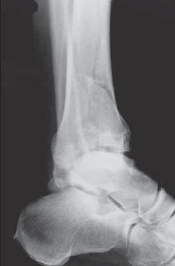

The diagnosis of tibial plafond fracture is initially evaluated with three radiographic views of the ankle (anteroposterior [AP], mortise, and lateral; FIG 4A,B).

CT scans have been clearly shown to improve a surgeon’s understanding of the injury ( FIG 4C) and are critical to preoperative planning for complex injuries.15

For displaced, comminuted pilon fractures, the best time to obtain a CT scan is after temporizing external fixation is performed ( FIG 4D), when the fracture is brought out to length with traction. This tends to grossly reduce many parts of the fracture, making the pathoanatomy of the injury more understandable (FIG 4E,F).

E F ### FIG 4 • 43-C3 tibial plafond injury. A,B. AP and lateral injury radiographs. C. CT scan. D. “Travelling traction”—early ankle-spanning external fixator. E,F. Radiographs of ankle after closed reduction and application of external fixator. G. Three-dimensional reconstruction of CT angiogram demonstrat- G ing deficient flow through anterior tibial artery.